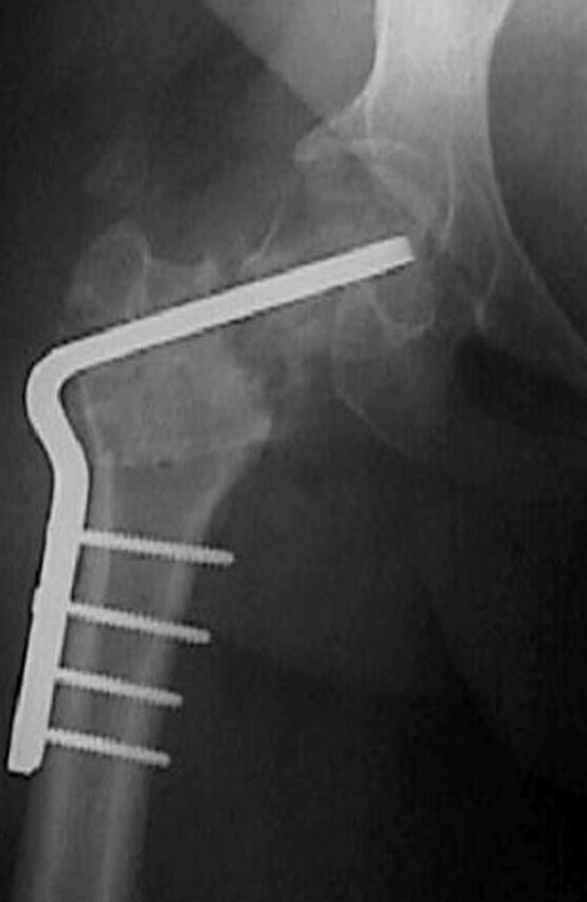

На рисунке N1 предоперационный план лечения ложного сустава шейки бедра- линия ложного сустава, угол и направление введения импланта, клиновидная остеотомия в градусах и миллиметрах, второй снимок после коррекции, расчет, на сколько удлиняется конечность и размеры импланта;

N3 рисунок окончательный снимок, после операции моя рентгенограмма должен выглядеть примерно как эта картина. На N4 снимке клин перед удалением; N5 послеоперации 3 нед.; N6 окончательная рентгенограмма.

(доложен в Ст. Петербурге 2003 и в Москве 2004)

варус при проксимальном отделе 95 градусной пластиной.